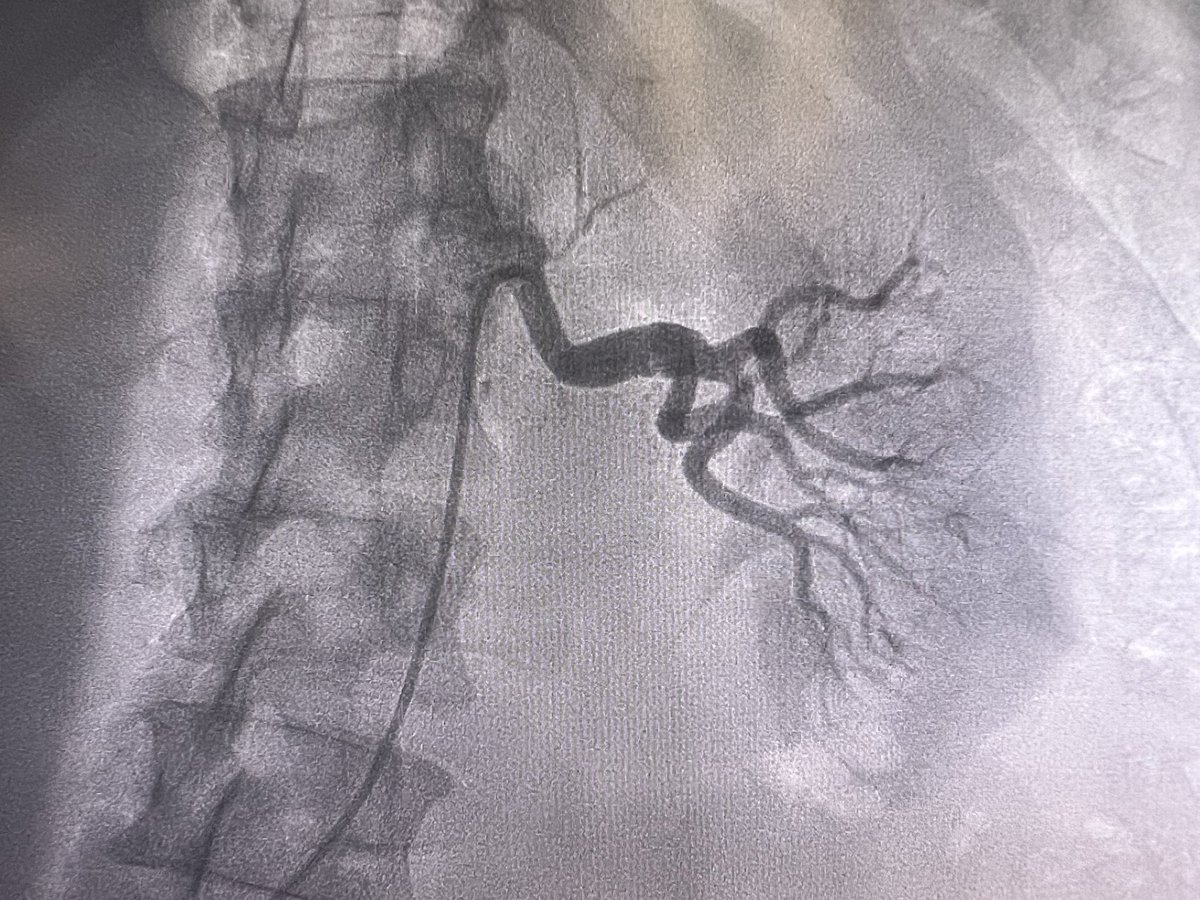

Proud to launch our official ECMO program at @mercy_health St Vincent Medical Center, Toledo. A step toward enhancing ability to care for sickest patients in community with life threatening cardio-pulmonary illnesses. Thanks to entire leadership and steering committee. @tcctoledo